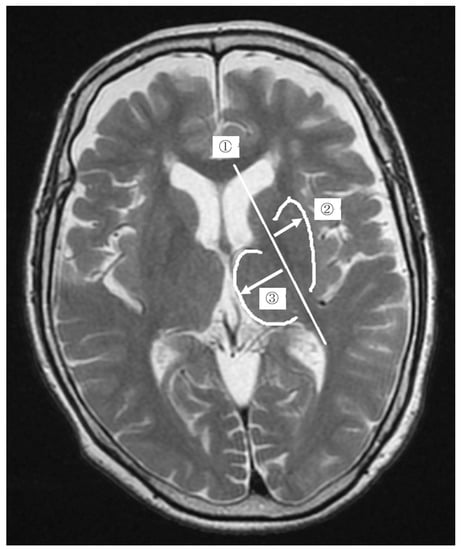

We used a built-in application of an electronic medical chart (HOPE/EGMAIN-GX, Fujitsu Limited, Tokyo, Japan) and measured anatomical distances on the images in increments of 0.01 mm. As shown in Figure 1, we defined the distances as the “putamen distance” and “thalamus distance”, respectively. During measurements, the MR images of the PD and control groups were presented randomly to the examiner. Measurements were performed independently by two physiotherapists with 11 and 9 years of clinical experience.

Figure 1. The measurement of the change ratio in the putamen using magnetic resonance images. First, we drew a straight line in the center of the posterior limb of the internal capsule and named it “the posterior limb of the internal capsule line” ➀. Second, we measured the distance from the posterior limb of the internal capsule line to the distal outline of the putamen (Right-pointing white arrow) and named it “putamen distance” ➁. Third, we measured the distance from the posterior limb of the internal capsule line to the distal outline of the thalamus (Left-pointing white arrow) and named it “thalamus distance” ➂. Finally, the ratio of putamen distance to thalamus distance was calculated, and the value was defined as the “change ratio in the putamen”.